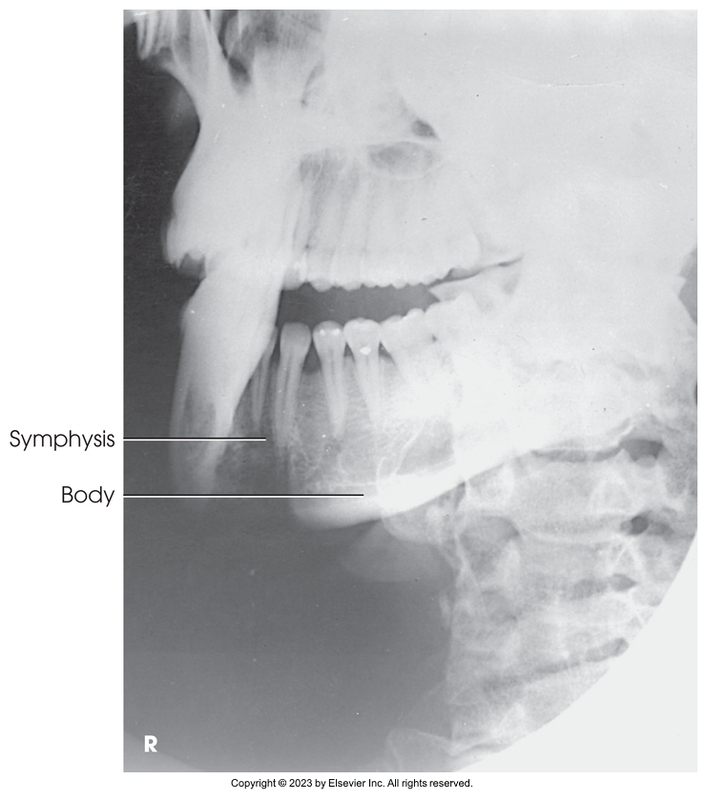

PA projection of mandibular body

Axiolateral oblique of the mandibular body

Axiolateral oblique of mandibular symphysis

PA of mandibular body

Axiolateral oblique of mandibular body

Axiolateral oblique of mandibular symphysis